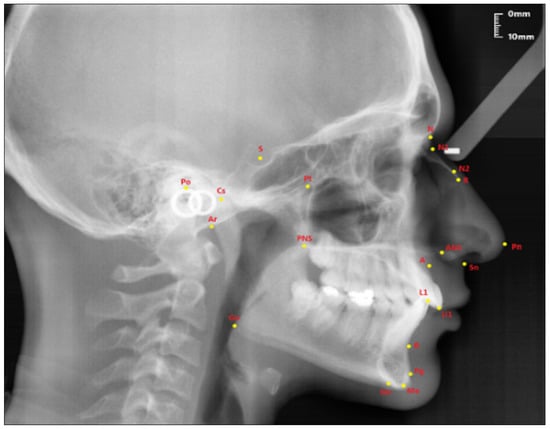

Figure 4.

Angular craniofacial skeletal measurements used in the study.

- SNA (°); the angle between the SN line and the NA line.

- SNB (°); the angle between the SN line and the NB line.

- ANB (°); the angle between the lines NA and NB.